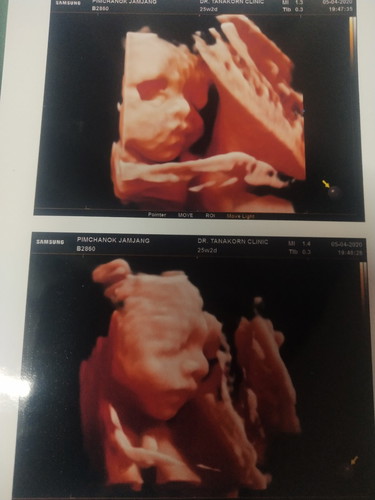

ท้อง 6 เดือน

ตอน 22 w จ้า วันนี้มีนัดกับคุณหมอ ซาวด์รอบนี้ 28 w น่าจะเห็นหน้าชัดเเล้ว 😍😍

แม่ซาวช่วงกี่วีคค่ะ ชัดมากเลย ซาวกี่มิติค่ะแบบนี้ราคาเท่าไหร่

จมูกโด่งมากค่ะ ขอให้แข็งแรงทั้งคุณแม่และลูกนะคะ💕